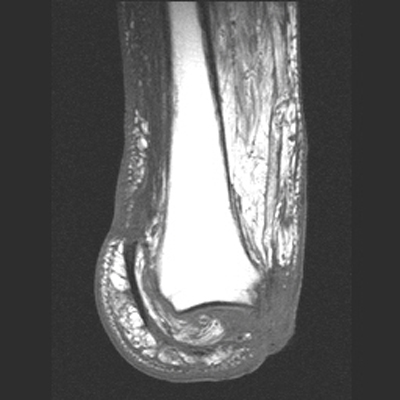

The MRI images below demonstrate the level of the Symes amputation along with bony and

soft tissue changes. Note the thick heel pad forming the majority of the distal

stump: the principle advantage of this procedure due to the more effective weight bearing.